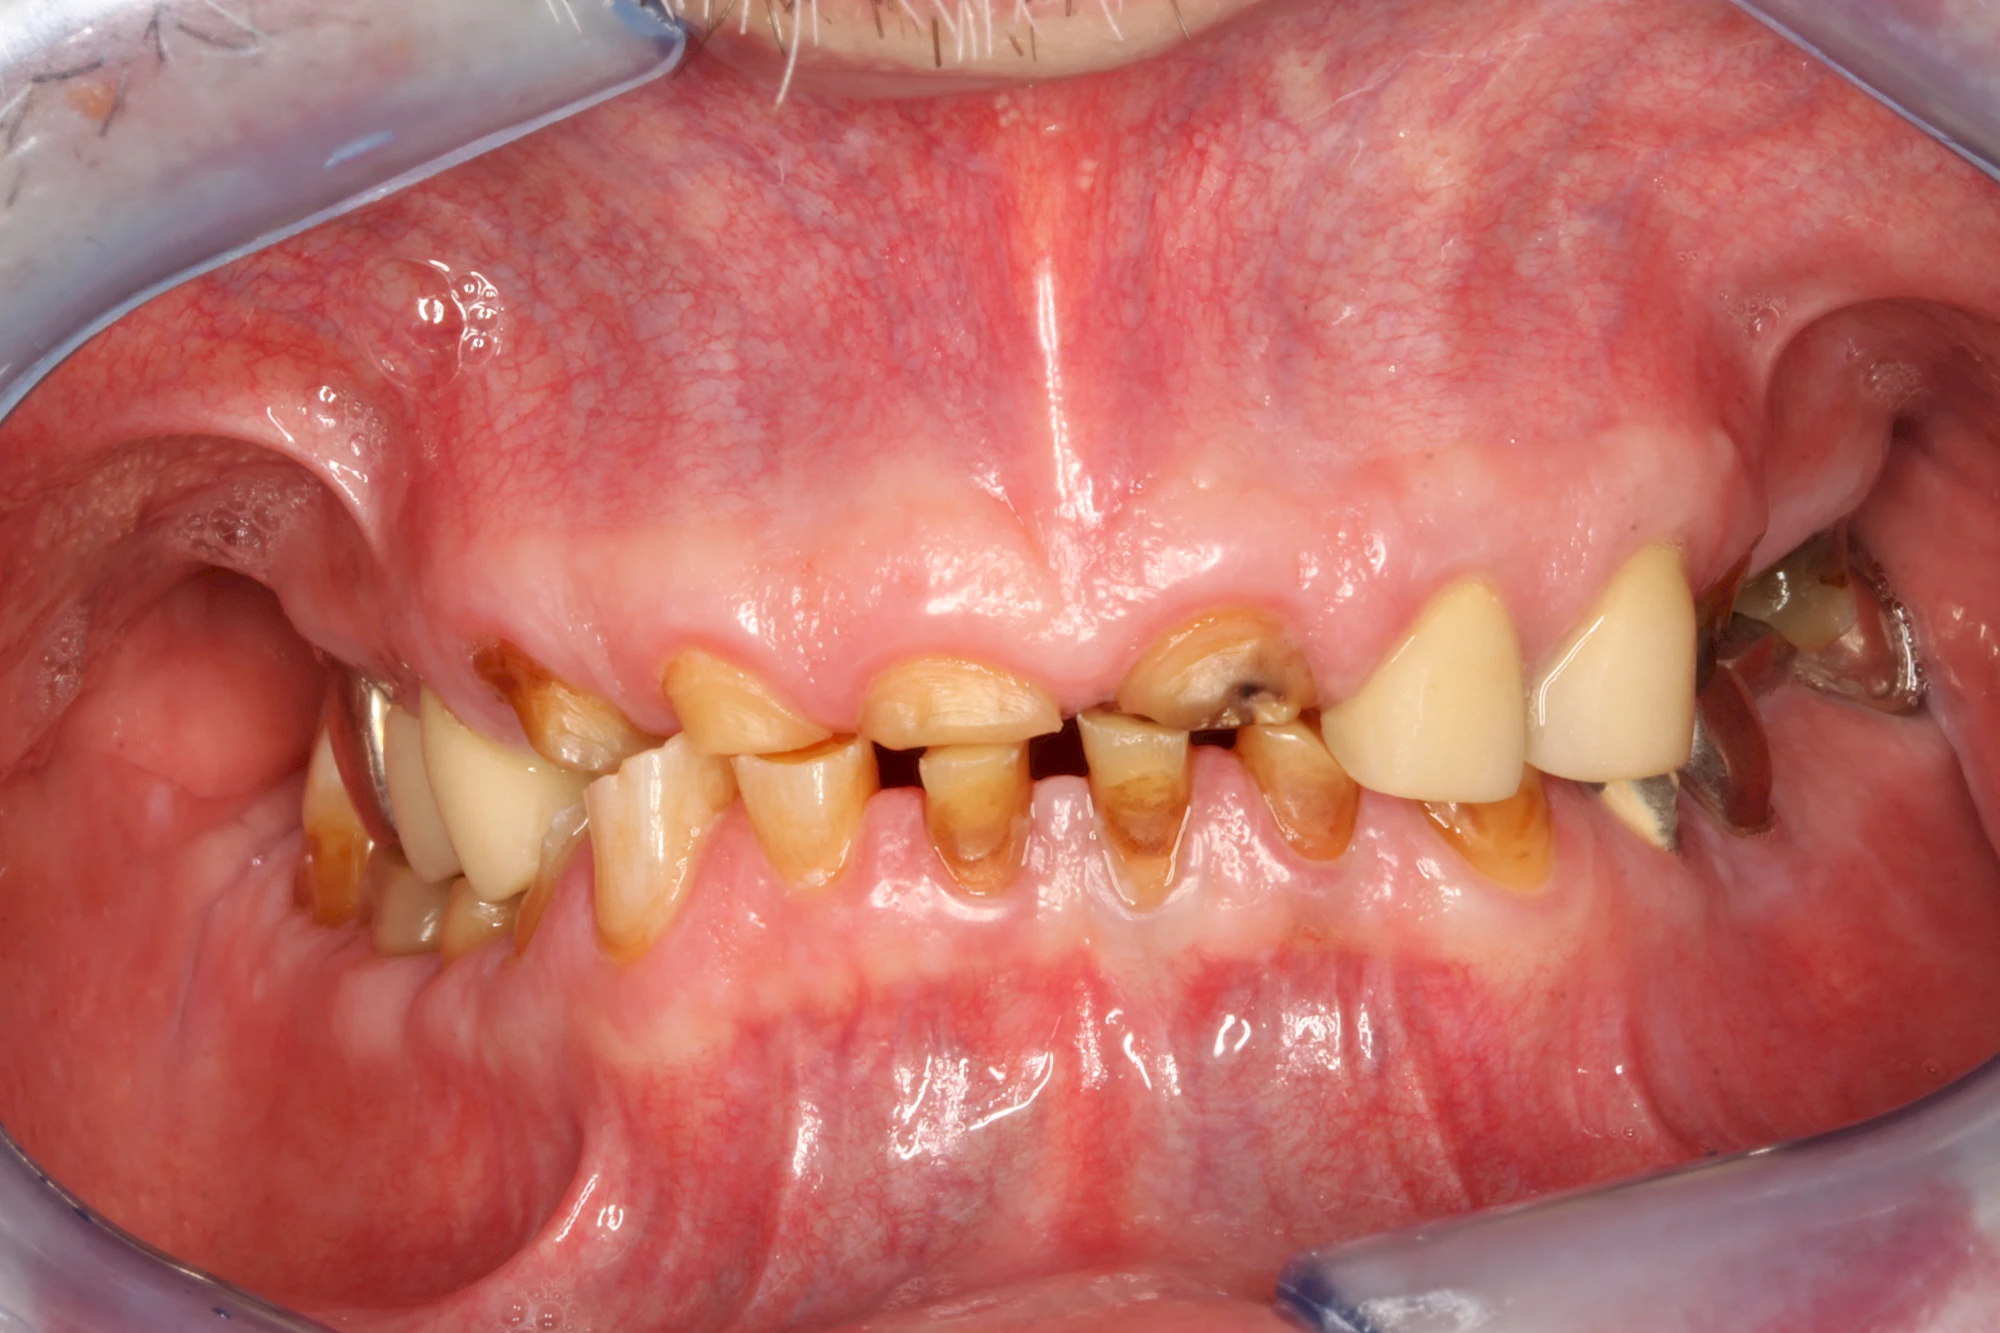

Über die Zeit können verschiedene Prozesse die Zahnhartsubstanzen aufzehren:

- Abnutzung durch Kauen (Abrasion) oder duch durch übermäßiges Knirschen bzw. Pressen (Attrition)

- Säurebedingte Auswaschung (Erosion)

- Knirschen bzw. Pressen und ungünstige Putztechnik (Druck): keilförmige Defekte

Die Zähne können dabei auf Reize (warm, kalt, süß, sauer) oder auch beim Zähneputzen empfindlich oder schmerzhaft sein. In allen diesen Fällen ist es sinnvoll, den Zahnarzt zu kontaktieren und das weitere Vorgehen abzustimmen.